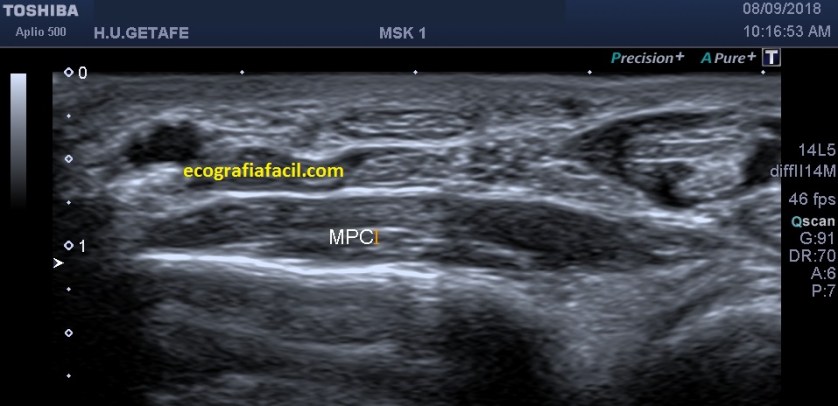

Lo primero normalidad:

En la inserción en el Calcáneo por la parte posterior las líneas amarillas marcan los diferentes grosores normales que adopta el tendón(hiperecogénico), desde su inserción distal hasta donde se hace más grande en el tercio distal de la pierna.

La flecha rosa marca una ligera cantidad de líquido normal que encontraremos justo encima de la línea hiperecogénica bajo el tendón y que corresponde con el calcáneo.

Cuanto más proximal es el tendón, más se aleja de la inserción, más fino se hace…